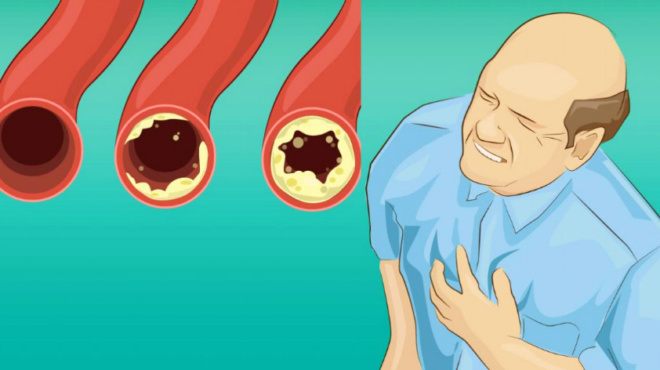

Ταχυπαλμία

Η ροή καλίου από και προς τα κύτταρα της καρδιάς συμβάλλει στον έλεγχο του καρδιακού παλμού. Όταν υπάρχει ελλειψη του από το σώμα μας τότε διαταράσσετε όλο το σύστημα.